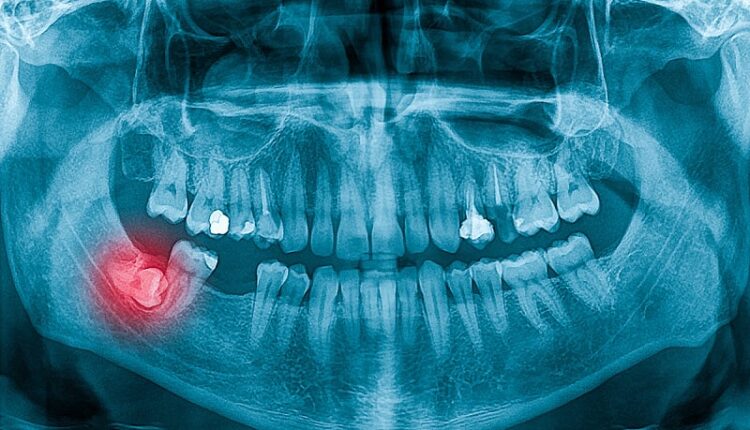

Истражувањето се фокусира на антителото USAG-1, кое е познато по тоа што го спречува развојот на забите кај цицачите. Во 2021 година, научниците од Универзитетот во Кјото, кои се дел од ова истражување, открија моноклонално антитело кое го нарушува взаимодействието на USAG-1 со коскените морфогенетски протеини (BMPs), кои играат клучна улога во формирањето на забите.

Во моментот, научниците го тестираат лекот на луѓе, во рамките на студија која трае 11 месеци и во која учествуваат 30 мажи на возраст од 30 до 64 години, кои имаат најмалку еден недостасувачки заб. Лекот се применува интравенски, а целта е да се оцени неговата безбедност и ефикасност. Во претходните студии на животни не се забележани негативни ефекти.